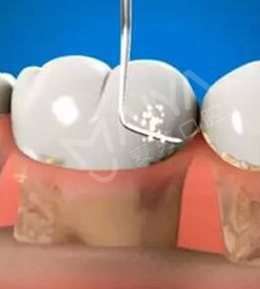

麦芽树脂补牙